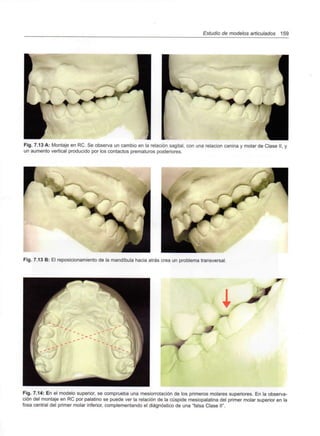

A. MATOS DA FONSECA